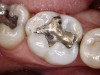

The benefits and ease of a universal bonding agent are demonstrated through the following case example of a Class II restoration. The patient was a 56-year-old woman. At her initial examination, it was observed that her lower right first molar (tooth No. 30) had an old failing amalgam restoration on the occlusal and a mesial fracture line with clinically visible caries (Figure 1). The preoperative bitewing x-ray did not show any mesial caries. The tooth needed a new restoration. The treatment plan was to perform a mesial-occlusal composite filling. A bitewing and periapical x-rays were taken to make sure that there was no other interproximal caries or any periapical lesion. Furthermore, an intraoral photograph taken with an intraoral camera was used to present and to help confirm the caries.

After anesthetic with 2% lidocaine with 1:100,000 epinephrine, a rubber dam was placed. The existing amalgam was removed using an inverted cone diamond bur and a small round diamond bur. The photograph showed recurrent and mesial caries. Removal of all the soft caries was performed using carbide round burs with a slow-speed handpiece. To make a clean and neat cavity preparation, all the superficial caries and stains were removed conservatively with a small round diamond bur. Then an intraoral photograph was taken to ensure that no caries was left behind (Figure 2).